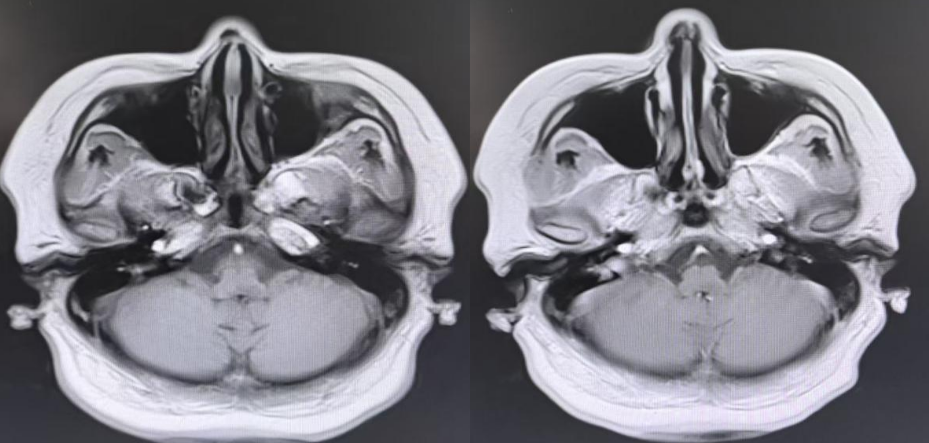

辅助检查:头部MRI:

头颅MR平扫+增强:

刘超团队的柳光林主治医师立刻为患者完善针对性检查与检验。头颅MR平扫+增强扫描结果显示:左侧延髓背侧见小片状长T1及长T2信号,弥散像未见信号明显增强,增强后无强化。结合临床考虑炎症。